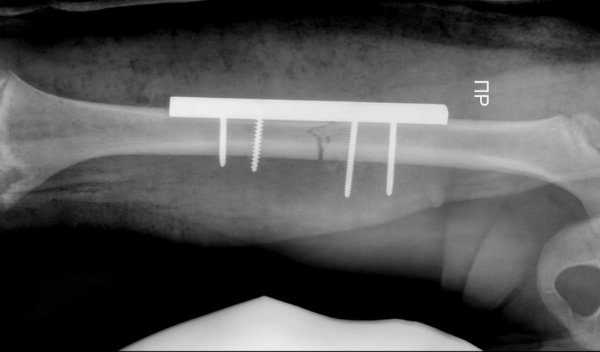

В стенах областной детской больницы впервые была проведена операция по установке гибких фиксирующих стержней, рассказал актауский общественник Азамат Сарсенбаев.

Врачам на этот раз пришлось повторно проводить операцию.

В течение часа детский хирург Курман Кайранов успешно заменил металлический на более современный гибкий стержень.

- Преимущество гибкого стержня заключается в том, что теперь при переломах больше не требуется делать большие разрезы в конечностях для установки фиксирующих стержней. Достаточно лишь сделать разрез в один сантиметр и вводить гибкий стержень под рентгеновским контролем, - рассказал Курман Кайранов.